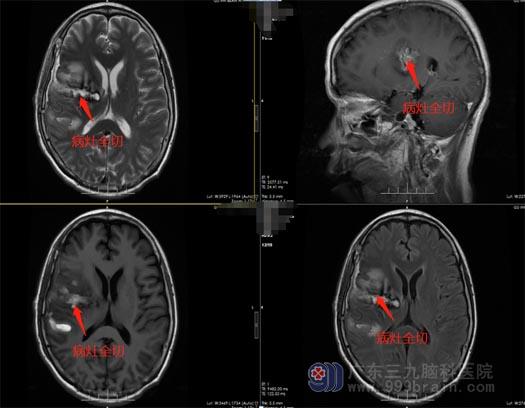

王国良分析:“肿瘤不仅波及范围大,而且周围有很多重要的血管、神经和脑组织,手术中分离肿瘤时需要保护好血管和神经,避免大出血和副损伤,所以手术难度非常大。”经过反复讨论后,最终确定为陈阿姨实施“右侧基底节-丘脑-放射冠区病变切除术”。术中在高清显微镜辅助下,先仔细分离血管,切除部分肿瘤,再磨开视神经管,一点一点地将肿瘤从神经上剥离下来。经过5小时的奋战,最终肿瘤被完全摘除,神经与血管均无损伤,顺利切除肿瘤大小约6cm×5cm×5cm。术后不到两个星期,陈阿姨康复出院了,头疼头晕和手臂无力的症状都有所改善。